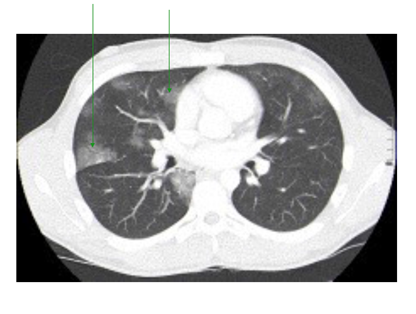

While still in the emergency department, he continued to have hemoptysis and developed palpable surgical emphysema at the root of the neck which raised suspicion of an ongoing air-leak from a TBI. A CT scan of the thorax was done and it showed a posterior tracheal tear 1.5cm above the carina as shown in Figure 2 and bilateral lung contusions, shown in Figure 3. His dyspnea and surgical emphysema continued to worsen, so he was intubated and immediately transferred to the nearest cardiothoracic centre.

Figure 3 CT Thorax transverse view showing lung contusions.